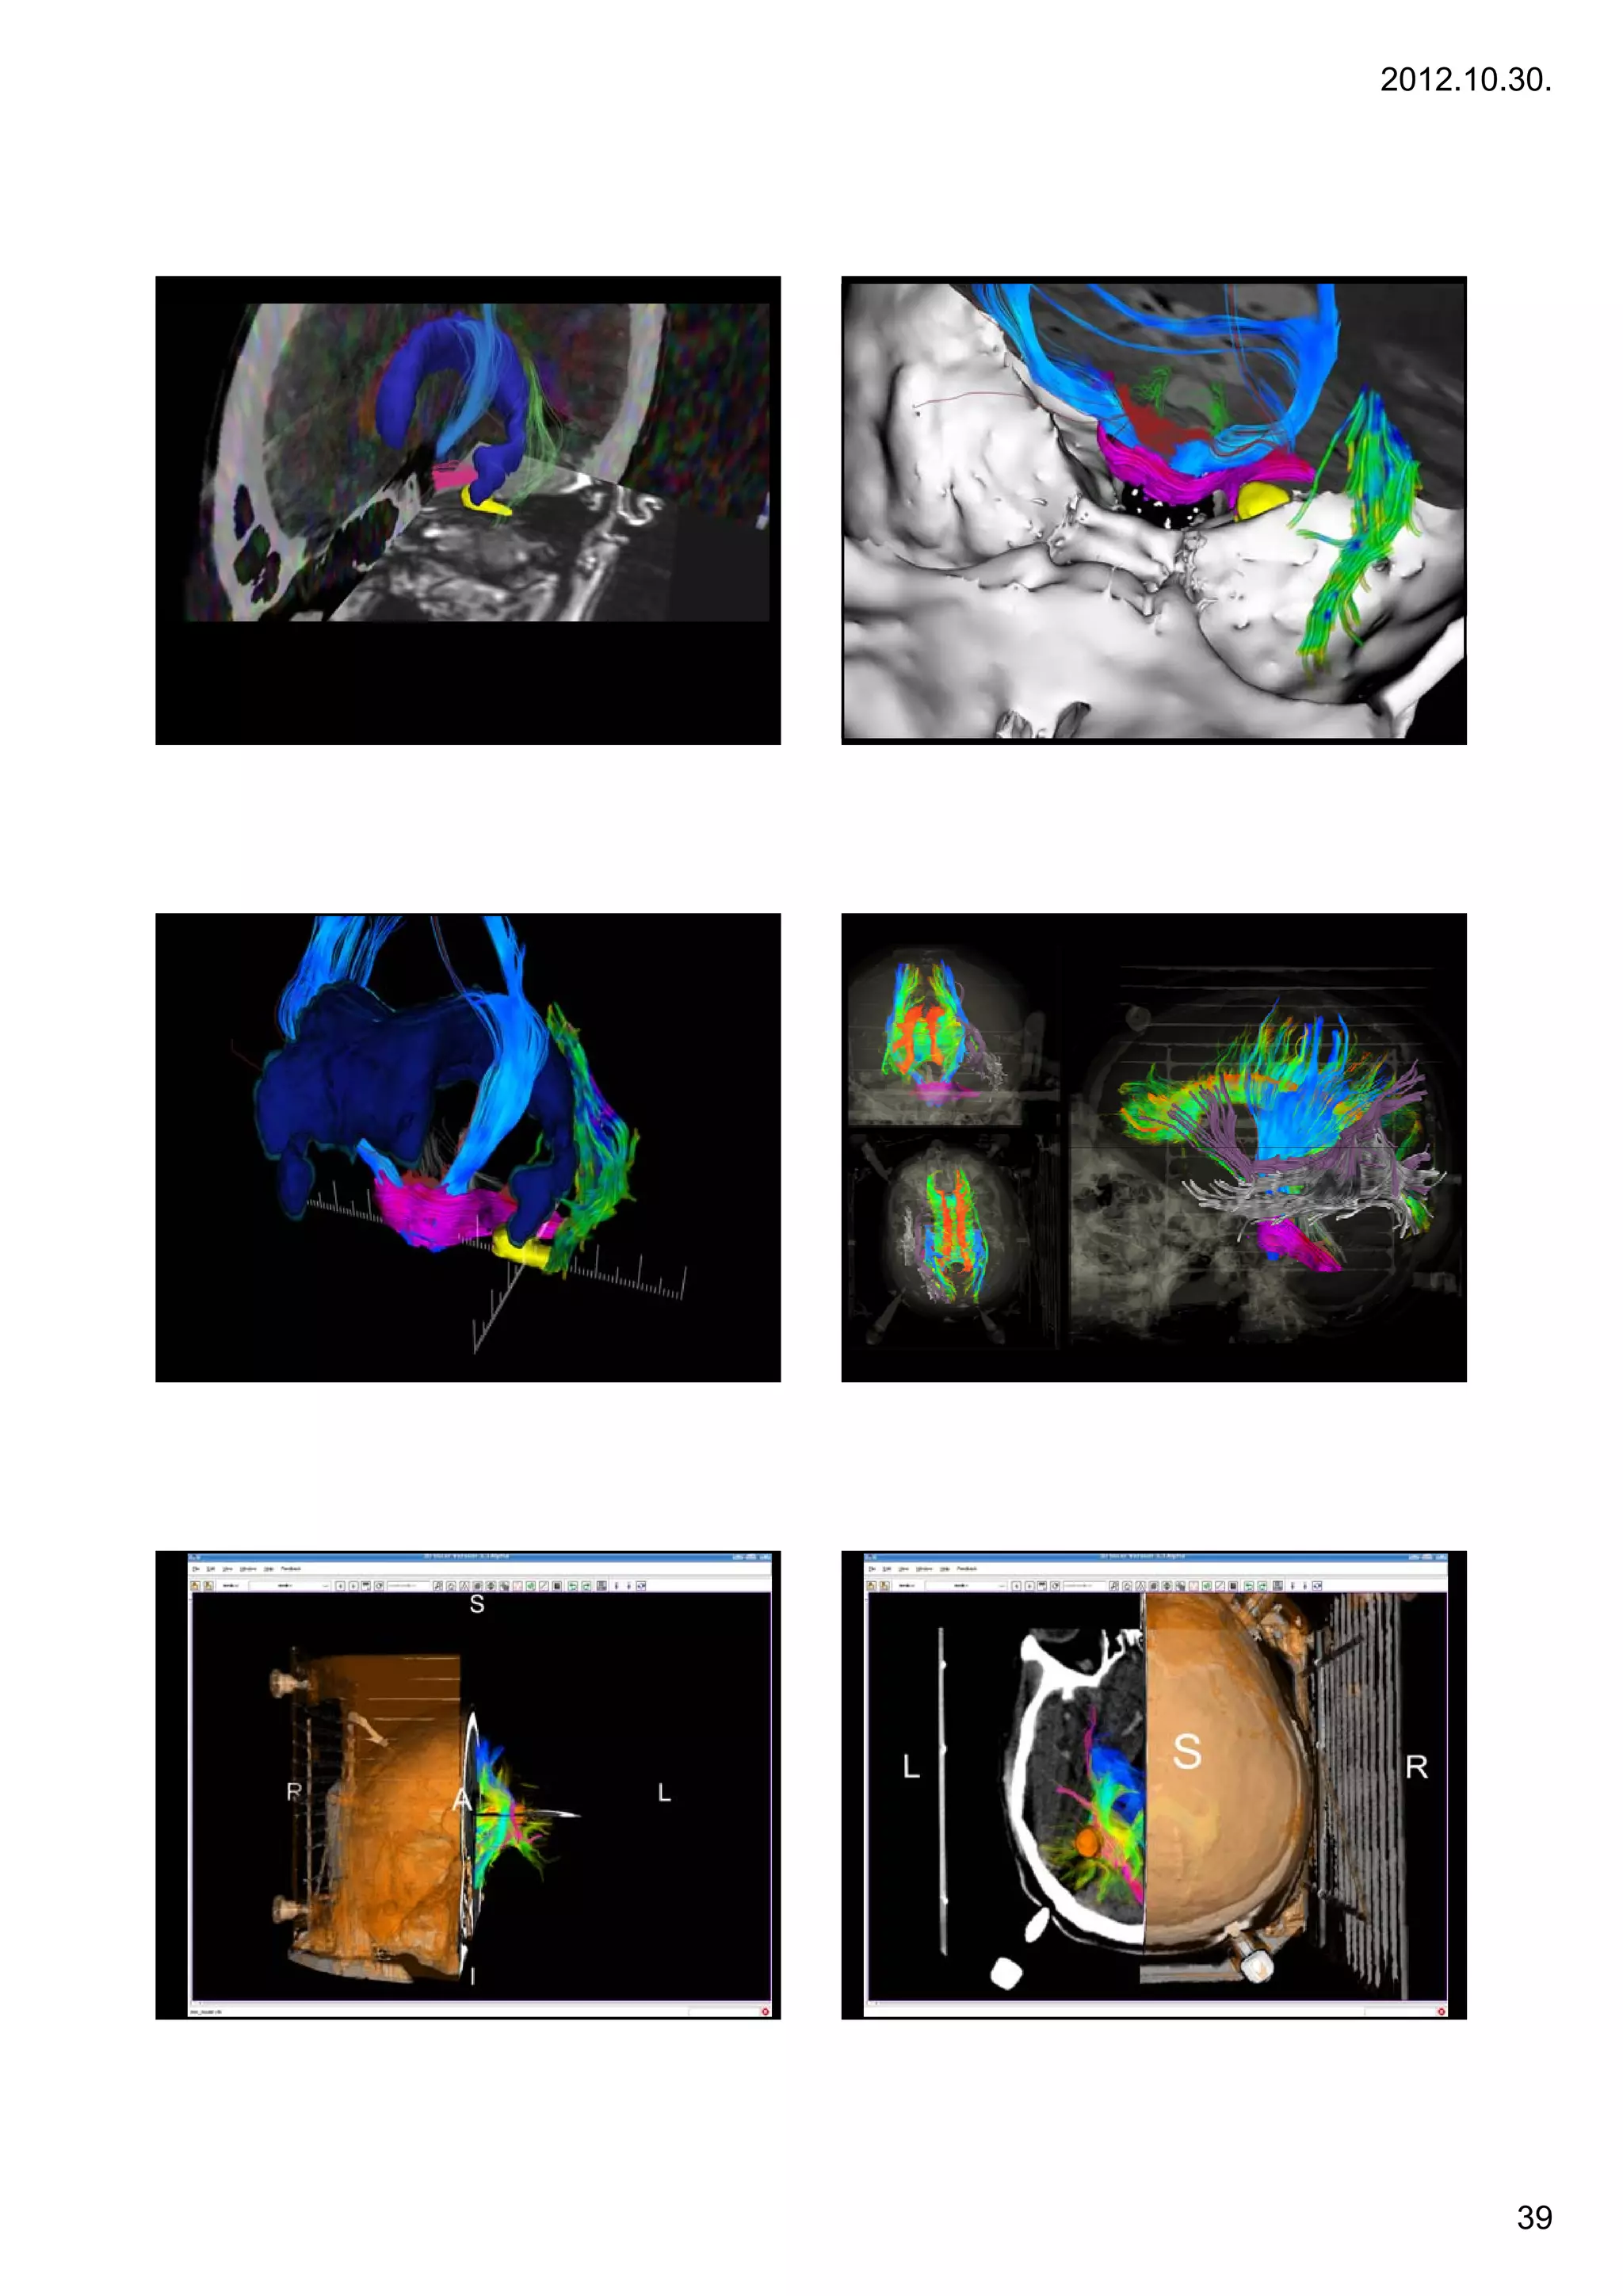

2012.10.30. Képregisztrációk (CT +DTI) Case 8 8. CT + ADC map CT + colorized FA map Acoustic neurinomas Acoustic neurinomas •A vestibular schwannoma, often called an acoustic neuroma,[1] is a benign primary intracranial tumor of the myelin-forming cells of the vestibulocochlear nerve(CN VIII).[2] The term "vestibular schwannoma" involves the vestibular portion of the 8th cranial nerve[3] and arises from Schwann cells, which are responsible for themyelin sheath in the peripheral nervous system. Approximately 3,000 cases are diagnosed each year in the United States with a prevalence of about 1 in 100,000 worldwide. It comprises 5-10% of all intracranial neoplasms in adults. Incidence peaks in the fifth and sixth decades and both sexes are affected equally. 28 éves nő 28 éves nő Acousticus neurinoma Acousticus neurinoma Gamma Sugársebészeti Központ Gamma Sugársebészeti Központ 38